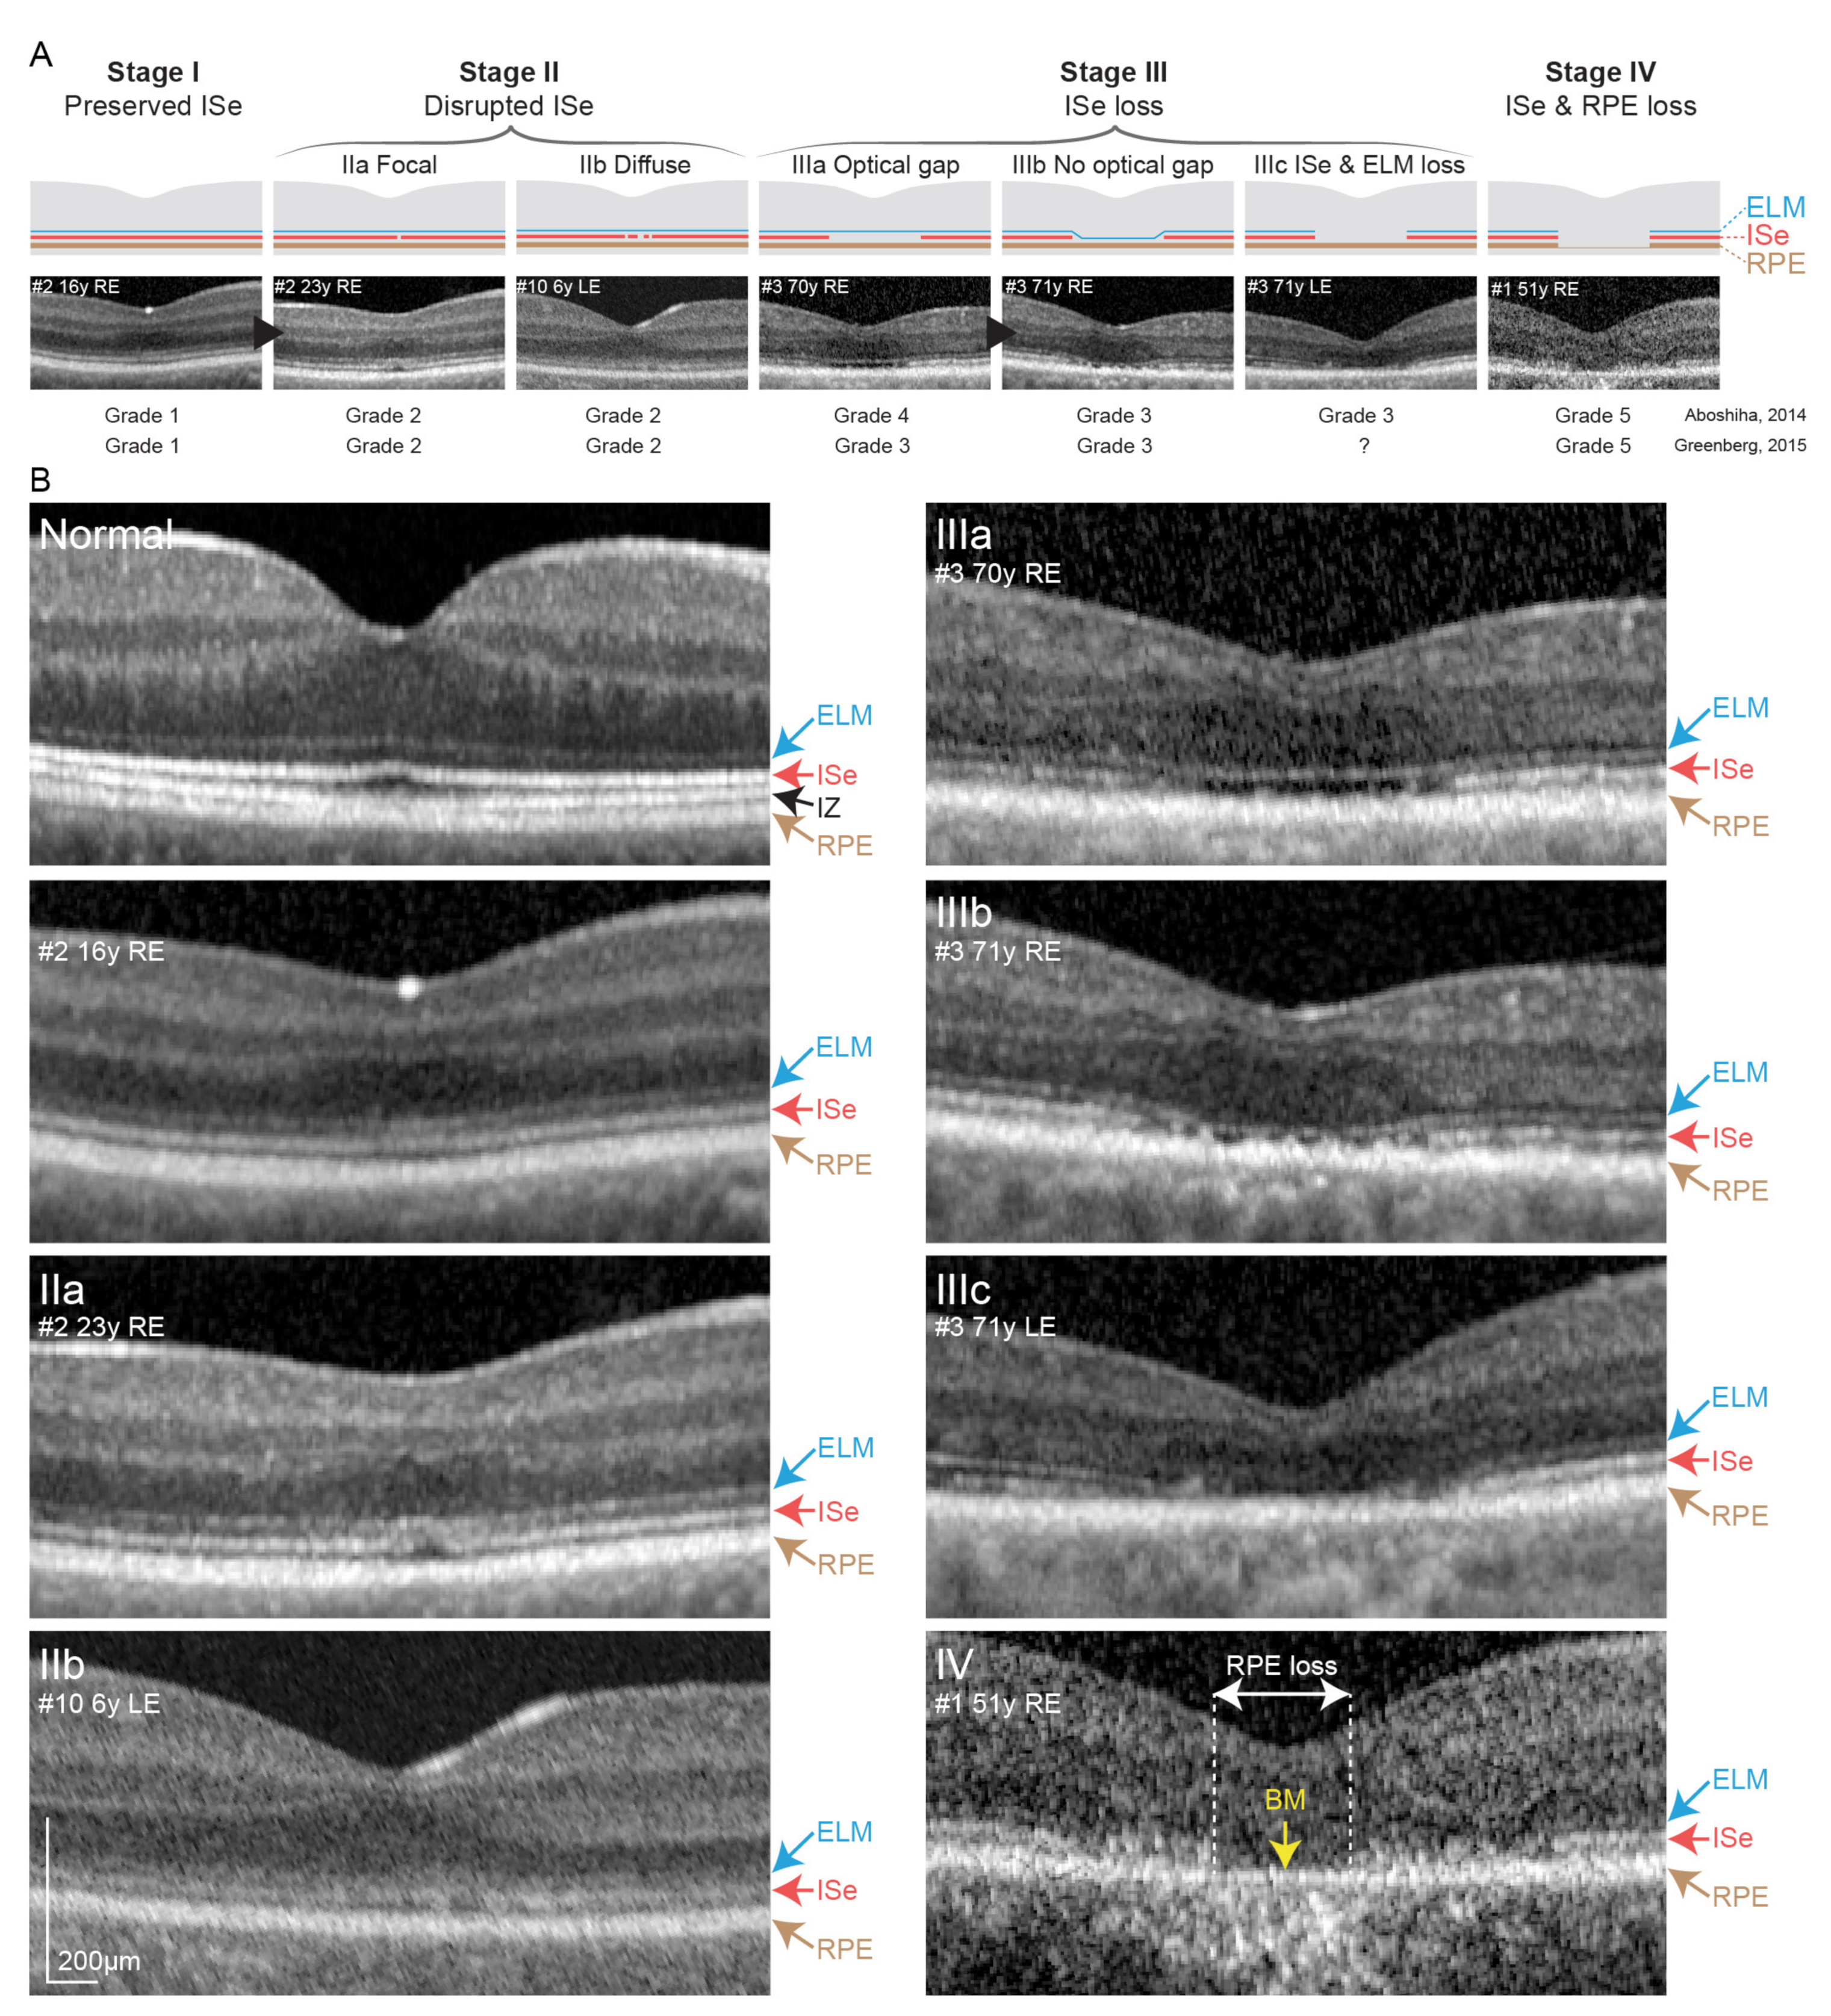

3.2.2. Optical Coherence Tomography and Fundus Autofluorescence Imaging